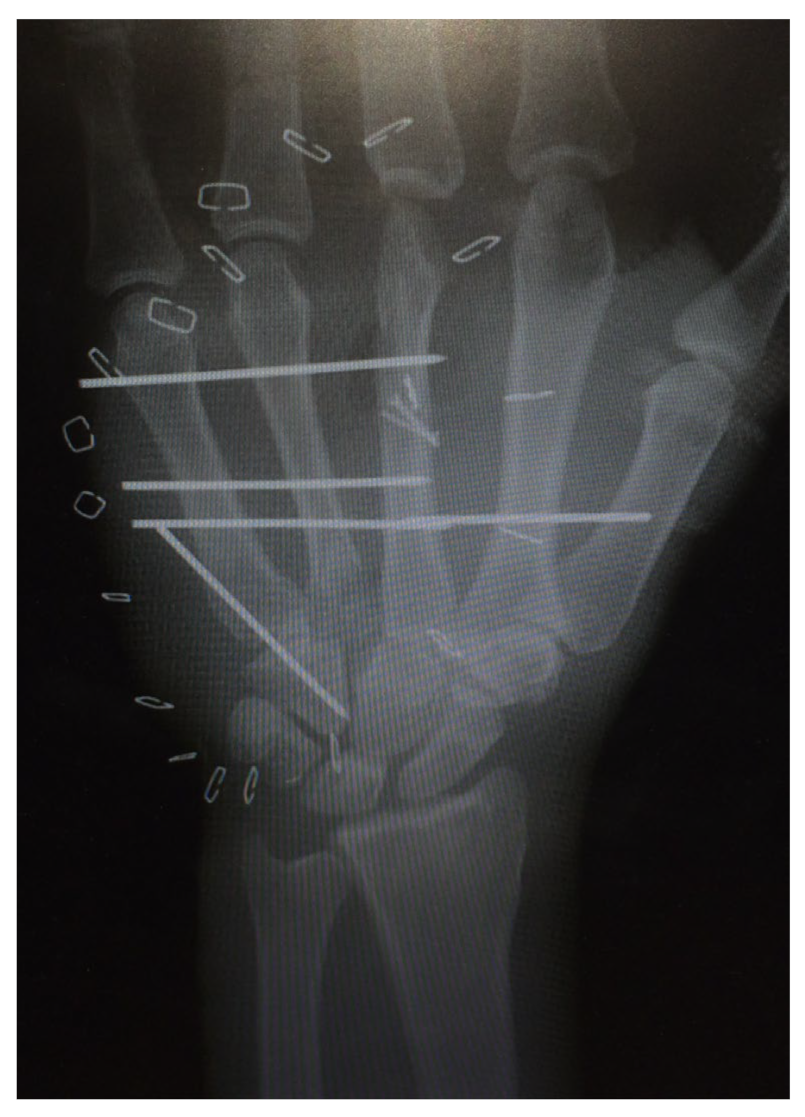

| 1 | 17 | m | Circular saw injury to the dominant left hand with a subtotal amputation of DII–DIV at the level of the MCP joints | Replantation of DIV Amputation of the distal metacarpals DII and DIII, PIP-Joint transfer to DII from the left second toe, MCP endoprosthesis DIII, Free double toe joint transfer to PIP and DIP from the right second toe | Finger-palm distance (FPD) DII–DV 0–0–1–0 cm Fingernail table distance (FNTD) DII–DV 0–0–0–0 cm Kapanji 10/10. DII: MCP 0–0–80°, PIP 0–0–100°, DIP 0–0–80°; DIII: MCP 0–0–80°, PIP 0–0–100°, DIP 0–0–50°; DIV: MCP 0–10–90°, PIP 0–0–90°, DIP 0–0–10°; DV: MCP 0–0–90°, PIP 0–0–100°, DIP 0–0–90°. | The two-point discrimination reached 4–6 mm in all fingers. | Pinch left 7 kg, right 10 kg. Force left 8 kg, right 18 kg. |